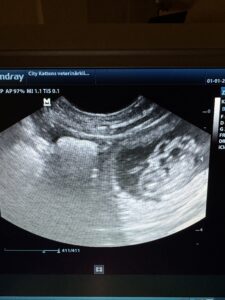

Up Swing Amazing Story ”Raya är dräktig med Sungold Maximillian Enzo.

Magen växer, blir nog många valpar.

Valparna planeras att födas trettonhelgen.